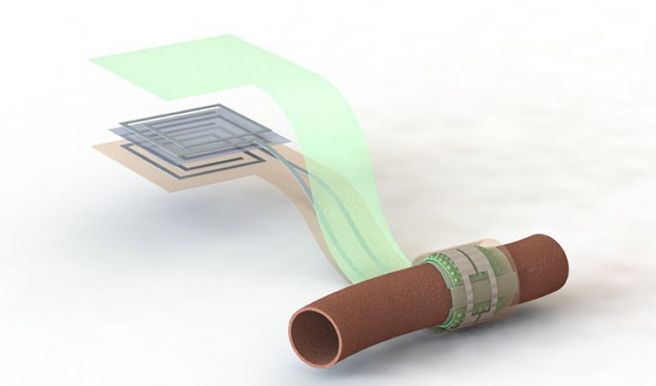

Esto llevó a un grupo de investigadores de la Universidad de Stanford a desarrollar un monitor de flujo sanguíneo biodegradable que puede envolverse alrededor de una arteria durante una cirugía vascular y luego monitorear el flujo sanguíneo.

El dispositivo sin batería y sin cable puede avisar al médico si un vaso está bloqueado, lo que les ayuda a abordar las complicaciones después de la cirugía

El dispositivo sin batería y sin cable puede avisar al médico si un vaso está bloqueado, lo que les ayuda a abordar las complicaciones después de la cirugía antes de que se conviertan en un problema más grave. Como el sensor es biodegradable, no necesita ser removido quirúrgicamente más tarde, simplemente se descompone y desaparece.

El recipiente pulsante distorsiona la superficie interna del sensor, lo que cambia su capacidad para almacenar una carga eléctrica. Esta propiedad puede medirse de forma inalámbrica mediante un dispositivo fuera del cuerpo, que se puede conectar a las antenas del sensor, lo que proporciona una medición inalámbrica del flujo sanguíneo para los médicos.